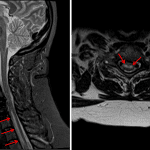

- Abnormal T2/STIR signal hyperintensity in the ventral cord largely involving gray matter extending from C6-T2 without substantial cord expansion or volume loss

- Spinal cord infarct

Abnormal T2/STIR signal hyperintensity in the ventral spinal cord extending from C6-T2, which appearance is primarily concerning for a cord infarct. Consider obtaining diffusion sequences for confirmation.